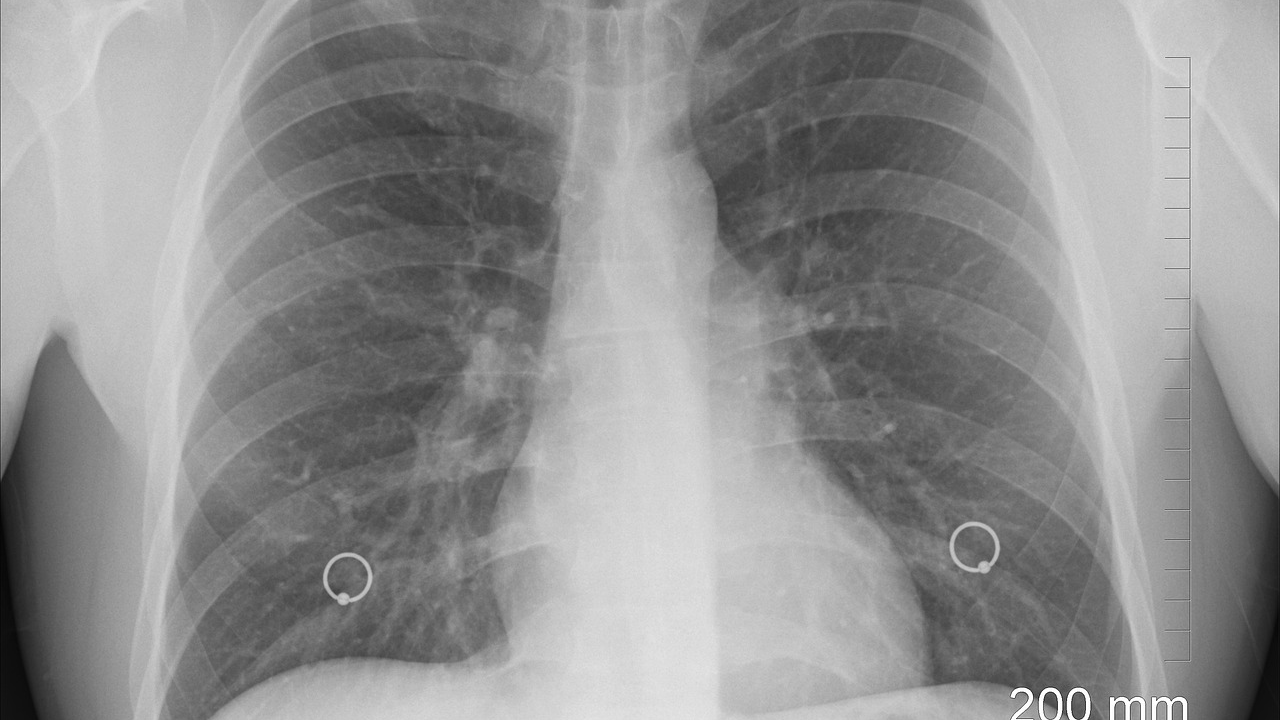

Opaka bolest u porastu, izdali upozorenje građanima

Zdravstveni dužnosnici u Engleskoj izdali su upozorenje nakon što su novi podaci pokazali značajan porast slučajeva tuberkuloze (TB), bolesti koja se smatra jednom od najsmrtonosnijom zaraznom bolešću na svijetu.

Liječnici upozoravaju da mnogi građani dugotrajni kašalj pripisuju gripi ili Covidu-19, dok bi uzrok zapravo mogla biti tuberkuloza – bolest koja je nekada bila gotovo iskorijenjena, ali se sada ponovno širi u pojedinim dijelovima zemlje. Tuberkuloza, uzrokovana bakterijom Mycobacterium tuberculosis, najčešće napada pluća, ali može zahvatiti i mozak, kralježnicu ili bubrege. Simptomi uključuju uporan kašalj dulji od tri tjedna (često s ispljuvkom ili krvlju), vrućicu, noćno znojenje, umor, gubitak težine i apetita. Ako se ne liječi, može uzrokovati trajna oštećenja pluća ili smrtonosne komplikacije poput meningitisa ili zatajenja organa, javlja Daily Mail.